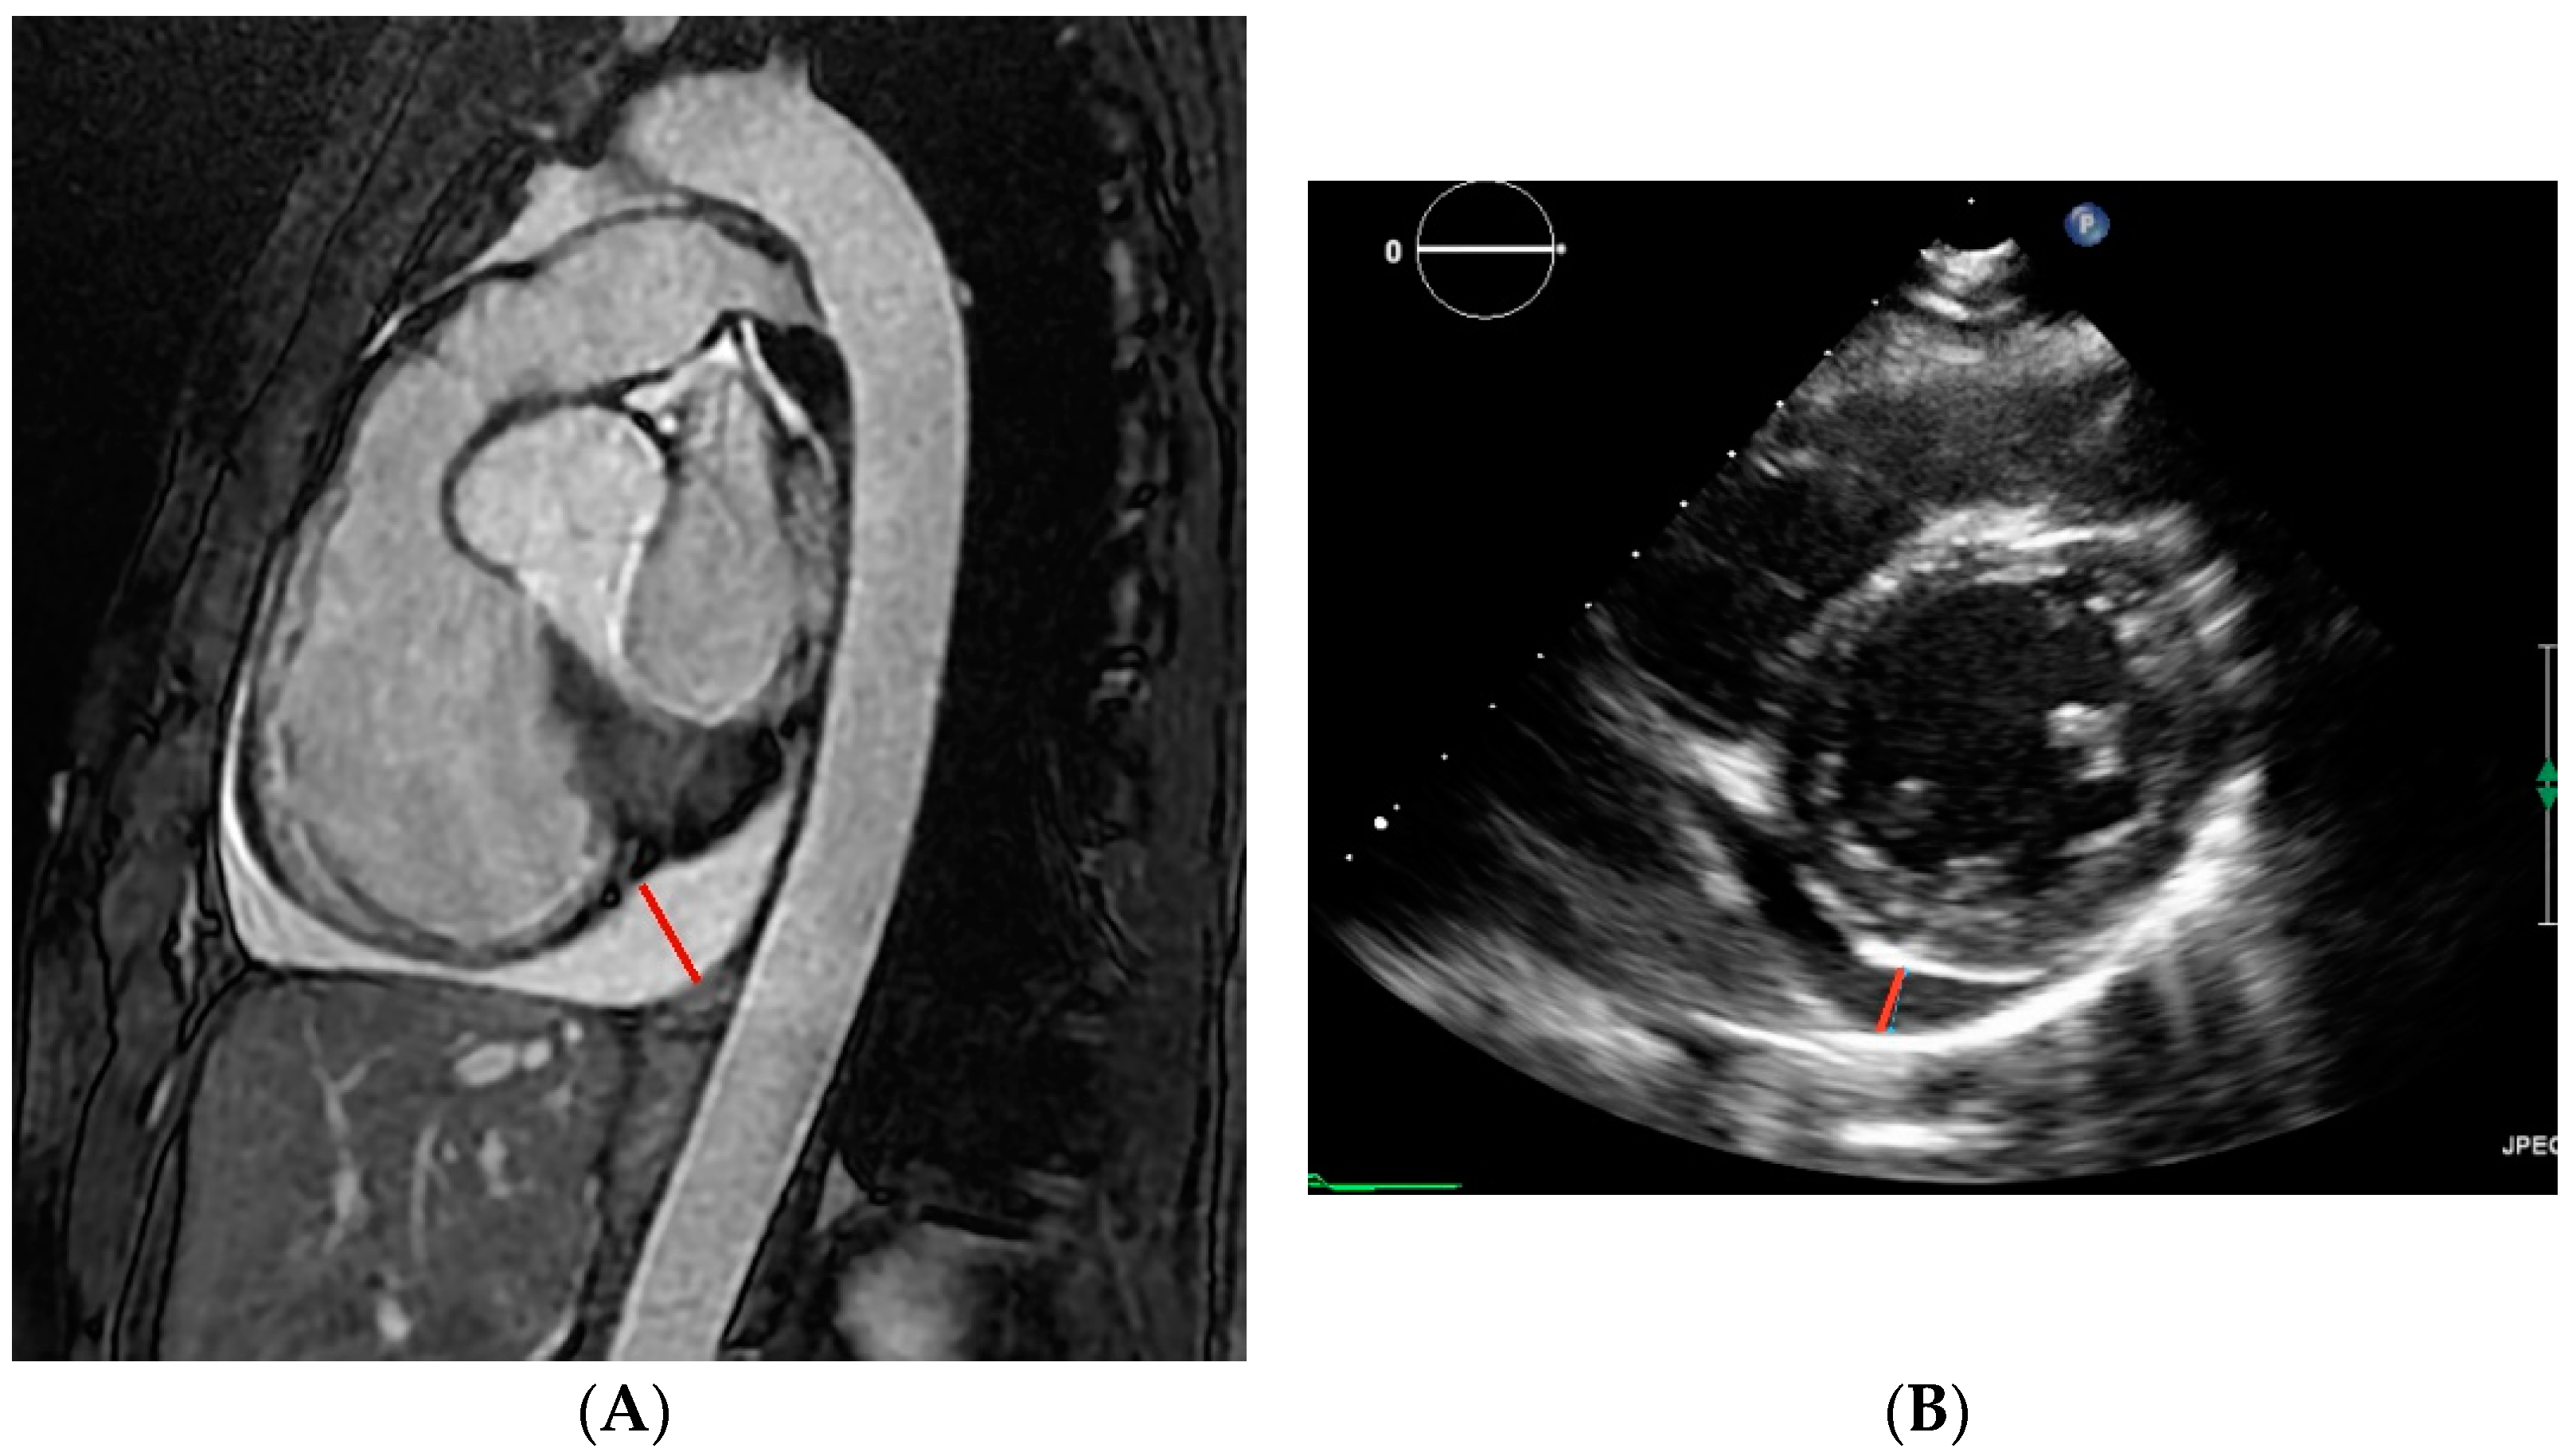

3.6. Genotype